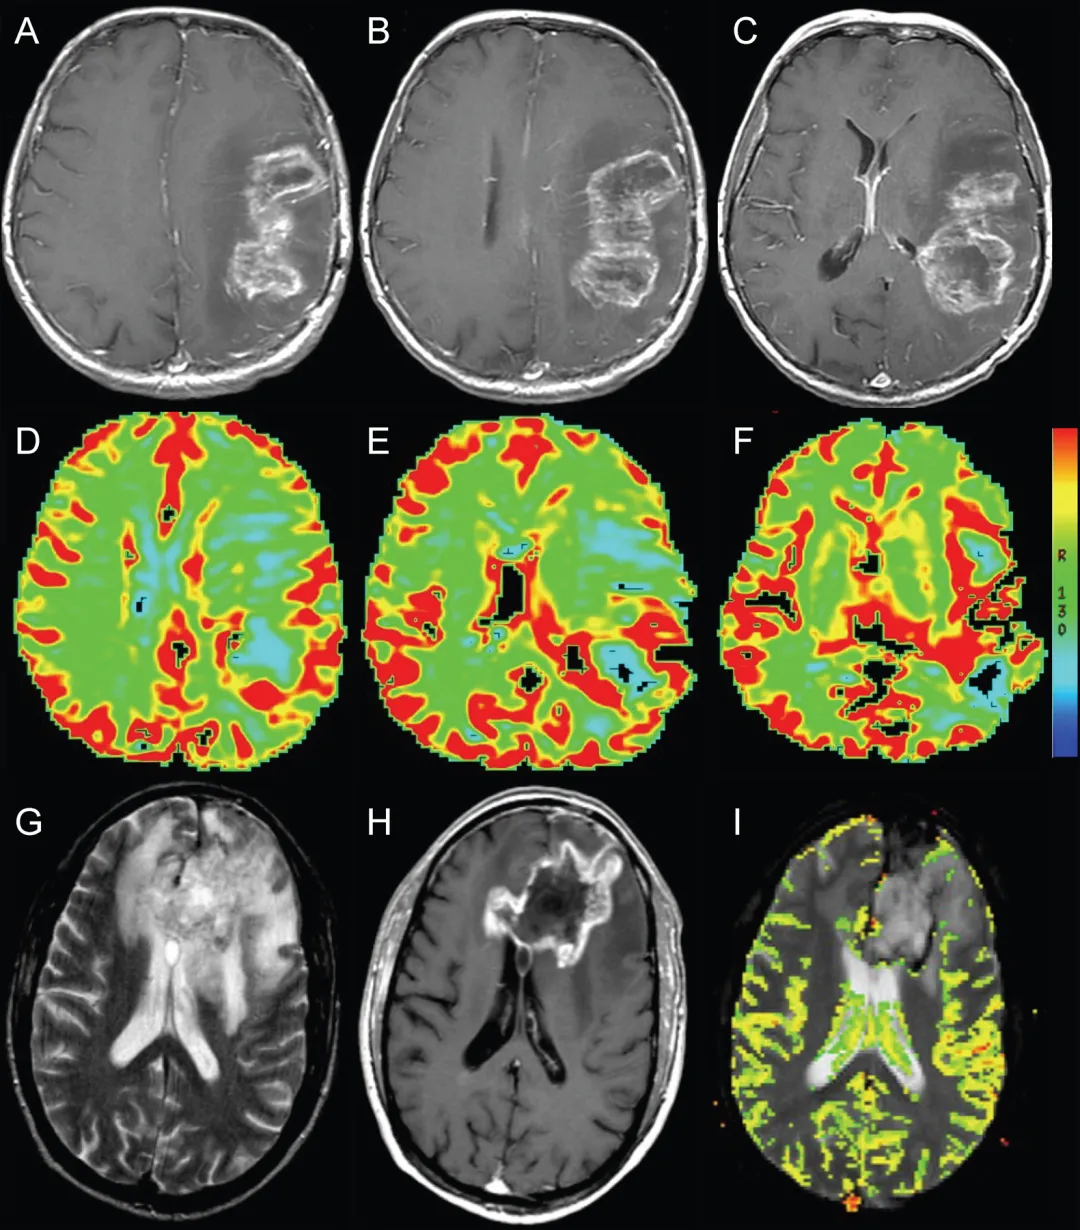

除传统T1、T2解剖序列外,其他磁共振成像序列有助于鉴别假性进展与真性进展——DSC、ASL、PET等。采用脑血容量作为灌注参数是识别真性进展的方法之一(图2、3),真性进展通常表现为血管化增加与灌注升高,而假性进展因其炎症病理生理机制常显示最小灌注相关改变。

图2.动态磁敏感对比灌注成像辅助鉴别假性进展。A-C:左侧额顶叶胶质母细胞瘤放疗后即刻轴位T1加权增强MRI,显示环形强化坏死性占位伴周围水肿及占位效应(与图1为同一患者)。D-F:轴位动态磁敏感对比灌注图像显示强化病灶后缘血容量轻度增加(箭头所示)。G:轴位T2加权MRI显示放疗后左侧额叶环形强化坏死性占位周围显着水肿,疑似肿瘤复发。H:轴位T1加权增强MRI显示结节状环形强化占位伴坏死。I:轴位动态磁敏感对比灌注图像未见血容量升高,符合假性进展病理诊断